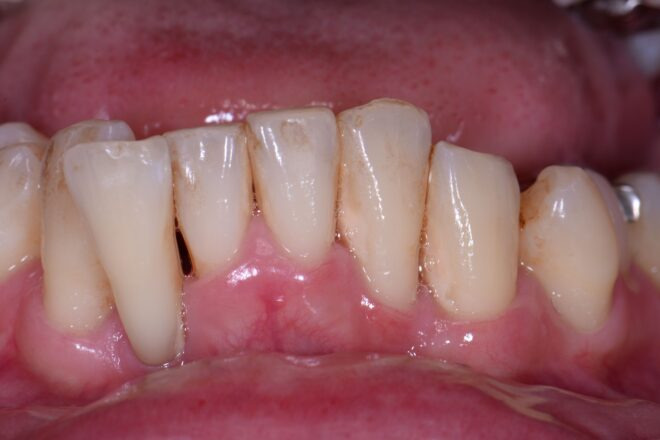

歯槽膿漏の症状が分かる写真は?

歯槽膿漏によって歯槽骨が溶け、歯茎が下がることで、歯が長く見えています。また、露出した歯根の周りには歯石が付着し、歯茎が腫れているのが分かるでしょう。歯槽骨が吸収されることで、歯がぐらつき、歯並びの悪化も招いてしまいます。